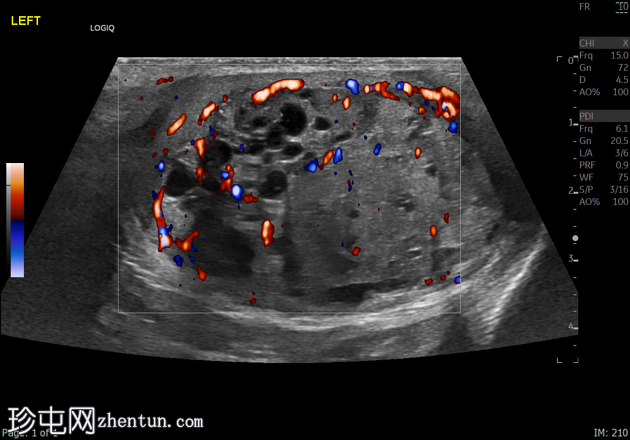

左侧睾丸肿大,体积约56 mL,可见弥漫性微结石,以及三个内部等回声病灶,伴囊性变、微钙化和明显血流信号,最大病灶大小约4.8 x 3.2 cm。

未见腹主动脉旁或髂淋巴结肿大。